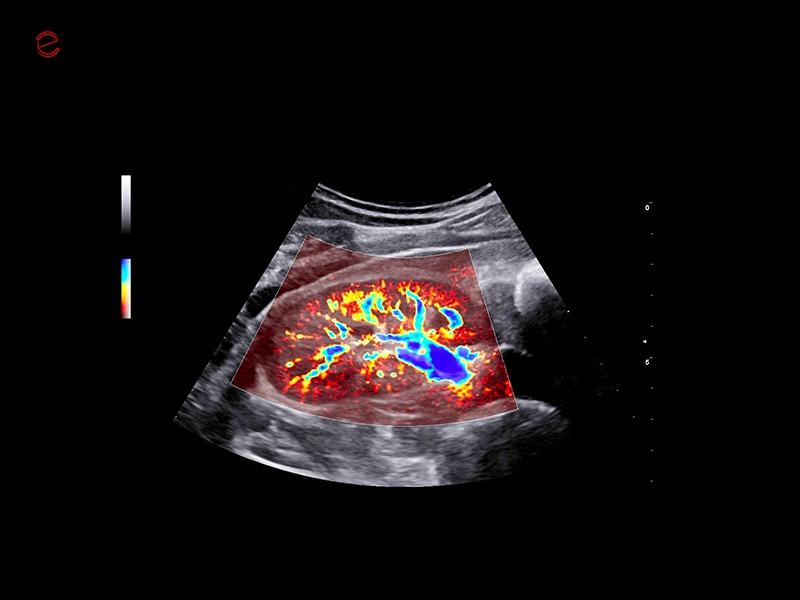

MyLab™9 Platform - XFlow Doppler enhancement in liver vascularization

MyLab™9 Platform - XFlow Doppler enhancement in liver vascularization

MyLab™9 Platform - Hemodynamics analysis using microV on kidney

MyLab™9 Platform - Hemodynamics analysis using microV on kidney